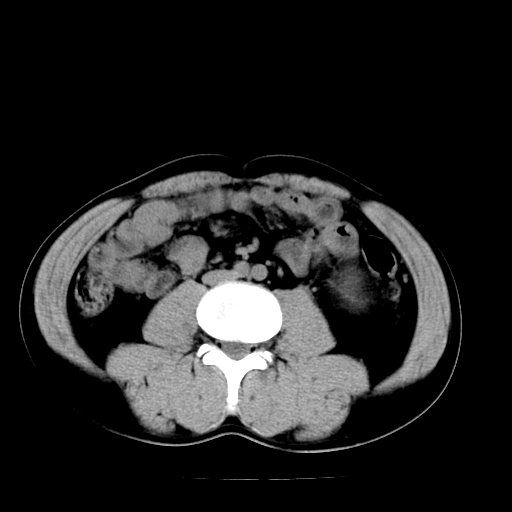

以下是引用天南地北在2007-4-30 13:36:00的发言:[br]支持慢性胰腺炎伴有假性囊肿

以下是引用andymaomao在2007-4-30 14:28:00的发言:[br]支持:1.慢性胰腺炎并假性囊肿形成可能;[br] 2.左肾形态稍增大,旋转不良。